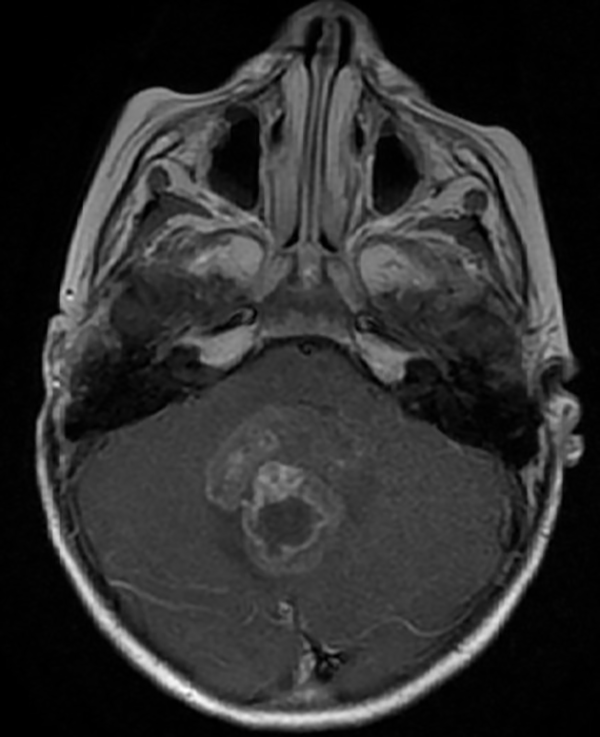

En resonancia magnética (RM) de cerebro se observa tumoración heterogénea sólida o sólido-quística con áreas de hemorragia, quistes y calcificaciones, que capta contraste en forma variable. (Fig. 1, 2, 3, 4). El patrón en espectroscopía se caracteriza por presentar pico de Colina (Cho) y descenso de N-Acetilaspartato (NAA).

Fig 2: RM corte sagital, secuencia T1 con contraste. Se observa neoformación medial, solido-quística, heterogénea de bordes irregulares en la topografía del VI ventrículo que ocupa la totalidad del mismo, que realza en forma heterogénea tras la administración del contraste y se proyecta caudalmente a través del foramen magno. Se evidencia colapso del VI ventrículo, desplazamiento del tronco cerebral hacia anterior y abombamiento del cuerpo calloso debido a la hidrocefalia obstructiva.